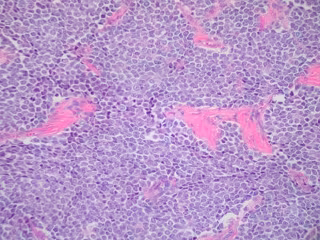

Sarcoma de Ewing

FLICKR/ED UTHMAN